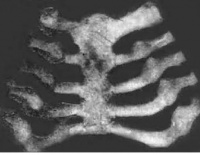

其他的骨骼变形有鸡胸、漏斗胸、X型腿、O型腿、肋串珠、手镯和脚镯,这些是比较严重的佝偻病才会出现的。现在已经很少见了。

①X线:钙化带模糊,干骺端增宽,边缘呈毛刷状或杯口状改变。

(一)临床分度:佝偻病的主要病理是骨样组织增生、骨基质钙化不良等骨骼变化。依据骨骼改变体征的程度可分为:

1、轻度:可见颅骨软化、囟门增大、轻度的方颅、串珠、肋软骨沟等改变。

2、中度:可见典型的串珠、手镯、肋软骨沟、轻度或中度的鸡胸、漏斗胸、O或X型腿,也可有囱门晚闭、出牙迟缓等明显的改变。

3、重度:可见明显的肋软骨沟、鸡胸、漏斗胸、脊柱畸型、O或X型腿、病理性骨折等严重改变。

2、激期:常见于3个月至2岁的小儿。有明显的夜惊、多汗、烦躁不安等症状。同时可有中度的骨骺改变体征。X线片可见临时钙化带模糊消失,干骺端增宽,边缘不整呈云絮状,毛刷状或杯口状,骨骺软骨加宽。血钙、血磷均降低,硷性磷酸酶增高。